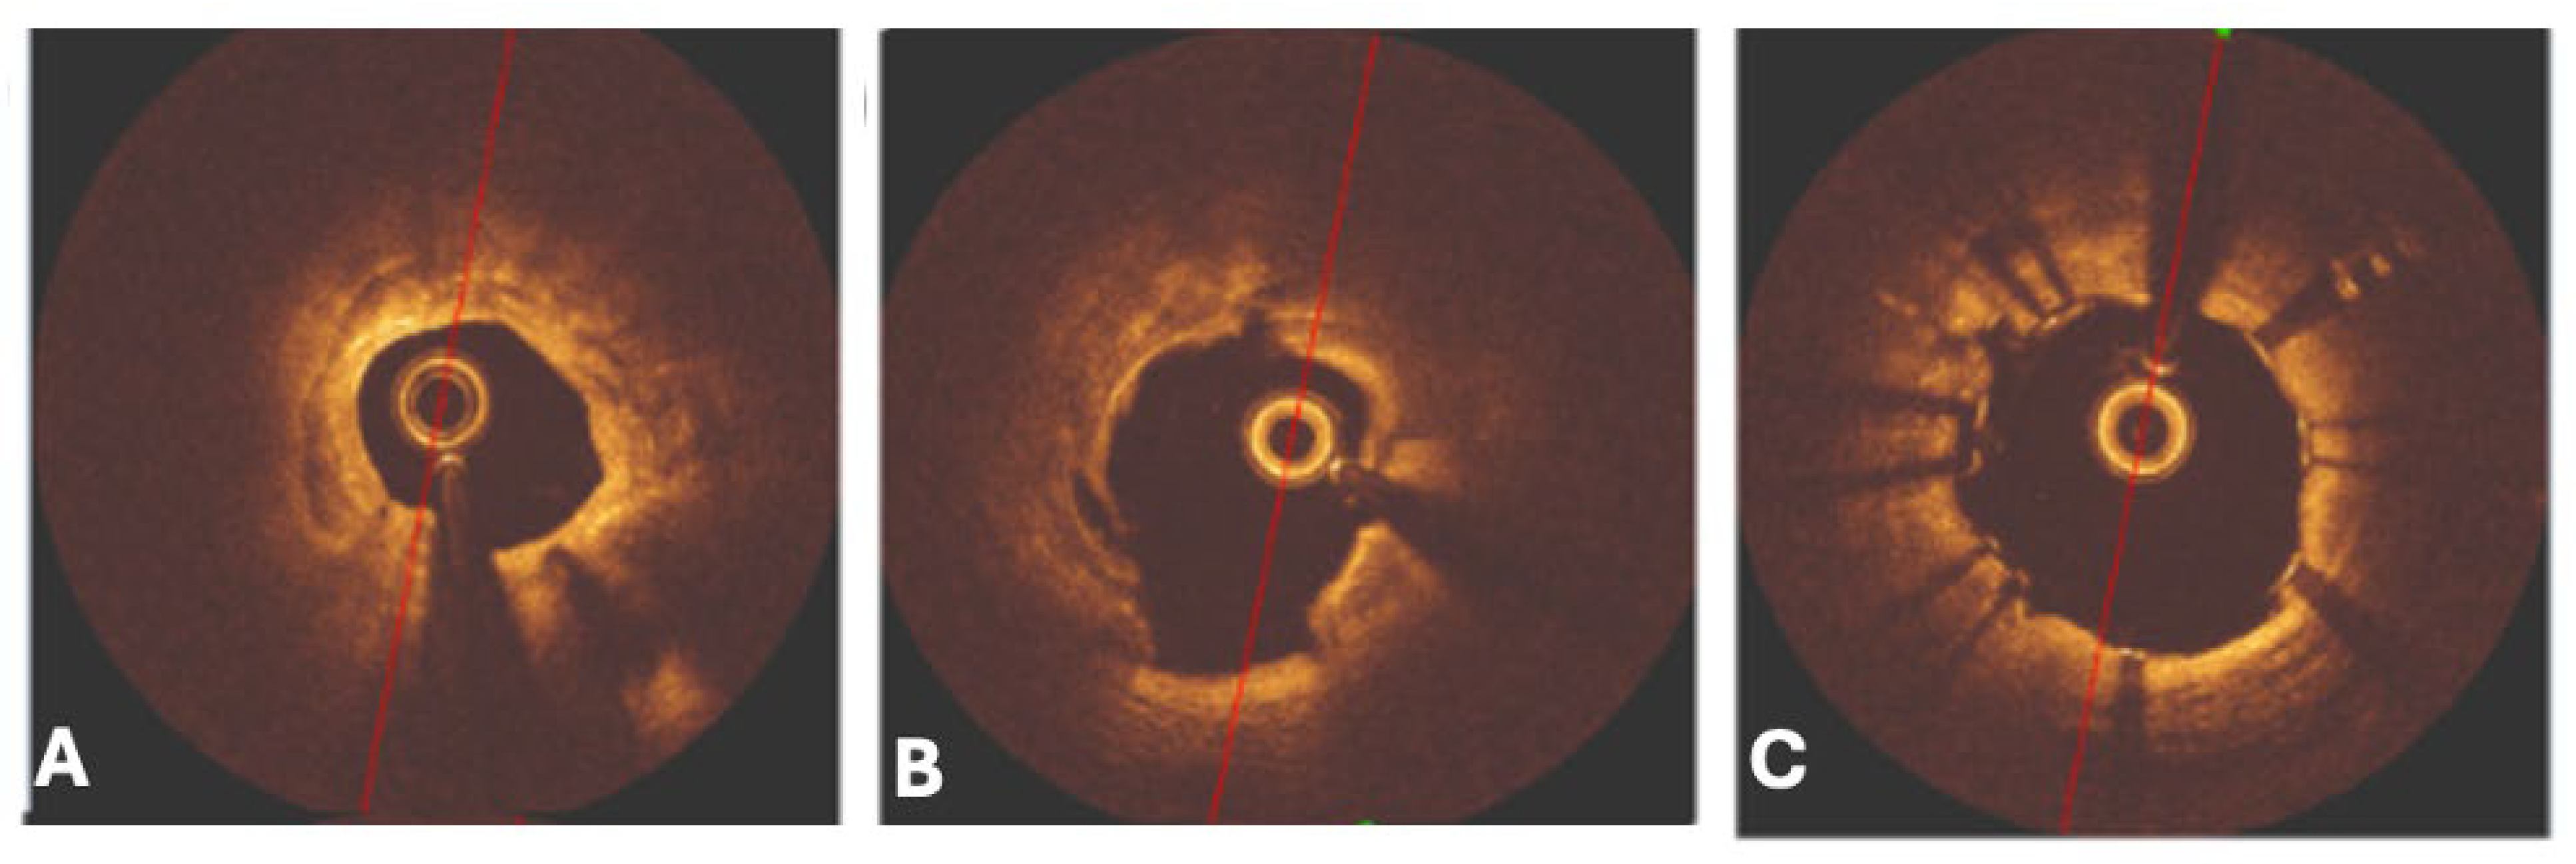

The effective execution and operation of intracoronary imaging modalities during these procedures improve both procedural and long-term clinical outcomes, particularly in intravascular ultrasound (IVUS) (Figure 6 and Figure 7) and optical coherence tomography (OCT) (Figure 8 and Figure 9), where coronary lesion morphology and mapping facilitate better PCI procedural planning [46]. Both IVUS and OCT can detect, localize, and quantify coronary calcification. Notably, OCT can visualize the calcified plaque without producing visual imaging artifacts, thereby minimizing observational scatter, and can evaluate calcium thickness more accurately than IVUS.

Intravascular ultrasound (IVUS) can provide information related to the arc, length, and superficial/deep texture of calcified plaques, but is restricted to the higher capabilities and superiority of optical coherence tomography (OCT), which can provide more than 10 times the spatial resolution of calcium deposits in the coronary walls when compared to the former imaging modality [33]. Both OCT and IVUS have demonstrated that CNs frequently present as eccentric, protruding calcific deposits disrupting luminal geometry. This morphology is associated with difficult wire passage, balloon slippage, and high rates of incomplete stent expansion, all of which translate into increased procedural complexity and suboptimal clinical outcomes [34,35].

6.5. Intravascular Lithotripsy

Intravascular lithotripsy (IVL) (Figure 15) is a minimally invasive procedure that utilizes acoustic shockwaves by generating high-amplitude ultrasonic pressure waves that vaporize the saline/contrast mixture within the balloon, causing it to induce circumferential calcium micro-fractures and fissures present within both the intimal and medial layers of the lumen [46,63]. The IVL catheter consists of an approximately 0.014-inch guidewire that is compatible with a balloon angioplasty catheter with two spark gap-based lithotripsy emitters incorporated into the shaft of the 12 mm-long balloon, and its indications to assess deep calcification and calcified nodules, large vessels, stent under-expansion (off-label), bifurcation lesions, and calcified aorto-ostial lesions are utilized [44].